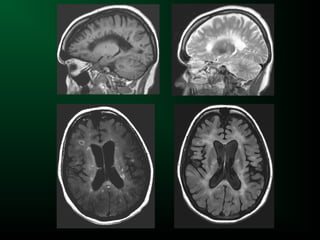

Système ventriculaire

normal

Hydrocéphalie

Hydrocéphalie active

Kyste

colloïde

Schwannome

vestibulaire

Contenu ventriculaire

Hémorragie

intraventriculaire

Abcès

Tumeur

Compression ventriculaire